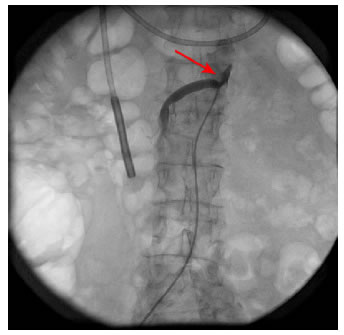

Fue hospitalizada en el servicio de geriatría; en la tomografía computarizada (TC) con contraste de abdomen se observó esteatosis hepática difusa, enfermedad arterioesclerótica aórtica grave y diverticulosis leve no complicada en el colon (figura 1). En el aortograma se documentó estenosis del 70 % de la arteria mesentérica superior y de la arteria renal derecha, del 30 % del tronco celiaco, del 40 % de la arteria mesentérica superior y del 90 % de la arteria iliaca común izquierda (figura 2).

Por el riesgo de trombosis mesentérica e isquemia intestinal grave, la paciente se sometió a una angioplastia periférica de la arteria mesentérica superior con colocación de una endoprótesis (stent), procedimiento se que llevó a cabo sin complicaciones (figura 3).